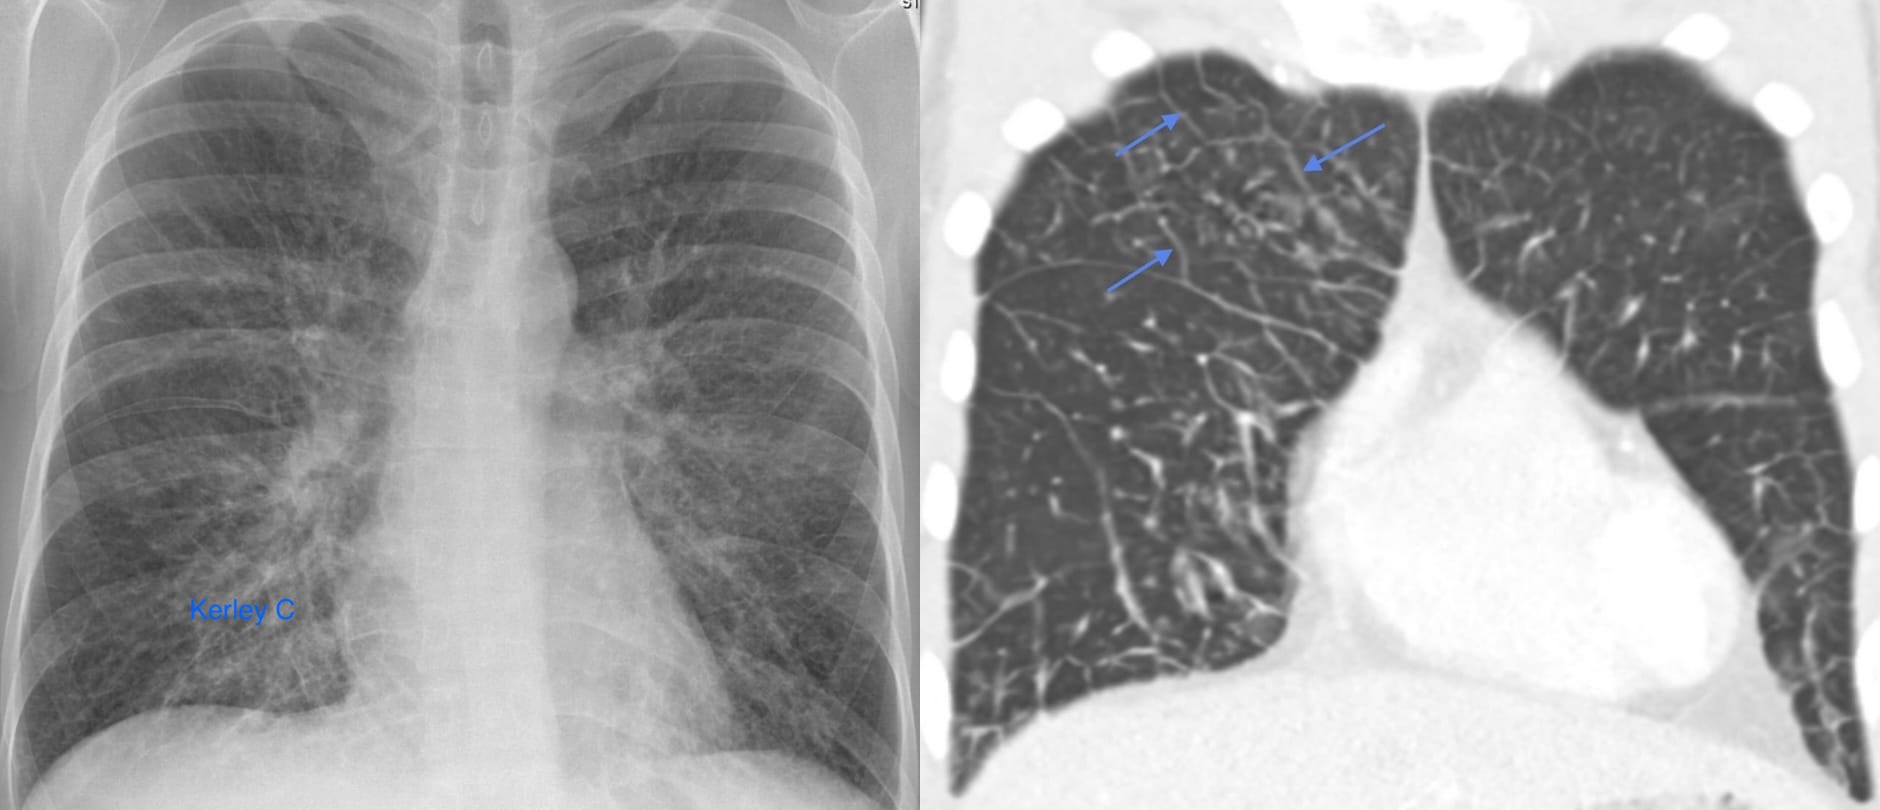

Interlobular septal edema

These represent interlobular septa, the connective-tissue-bearing structures, separating one lobule from its neighbor, distended with fluid and rendered visible.

Traditionally, the horizontally-oriented, short lines above the lateral costophrenic sulci on frontal radiography are termed Kerley B lines; those in proximity to the hila, Kerley A lines; and those imaged en face, perceptually a reticular-type network, Kerley C lines.